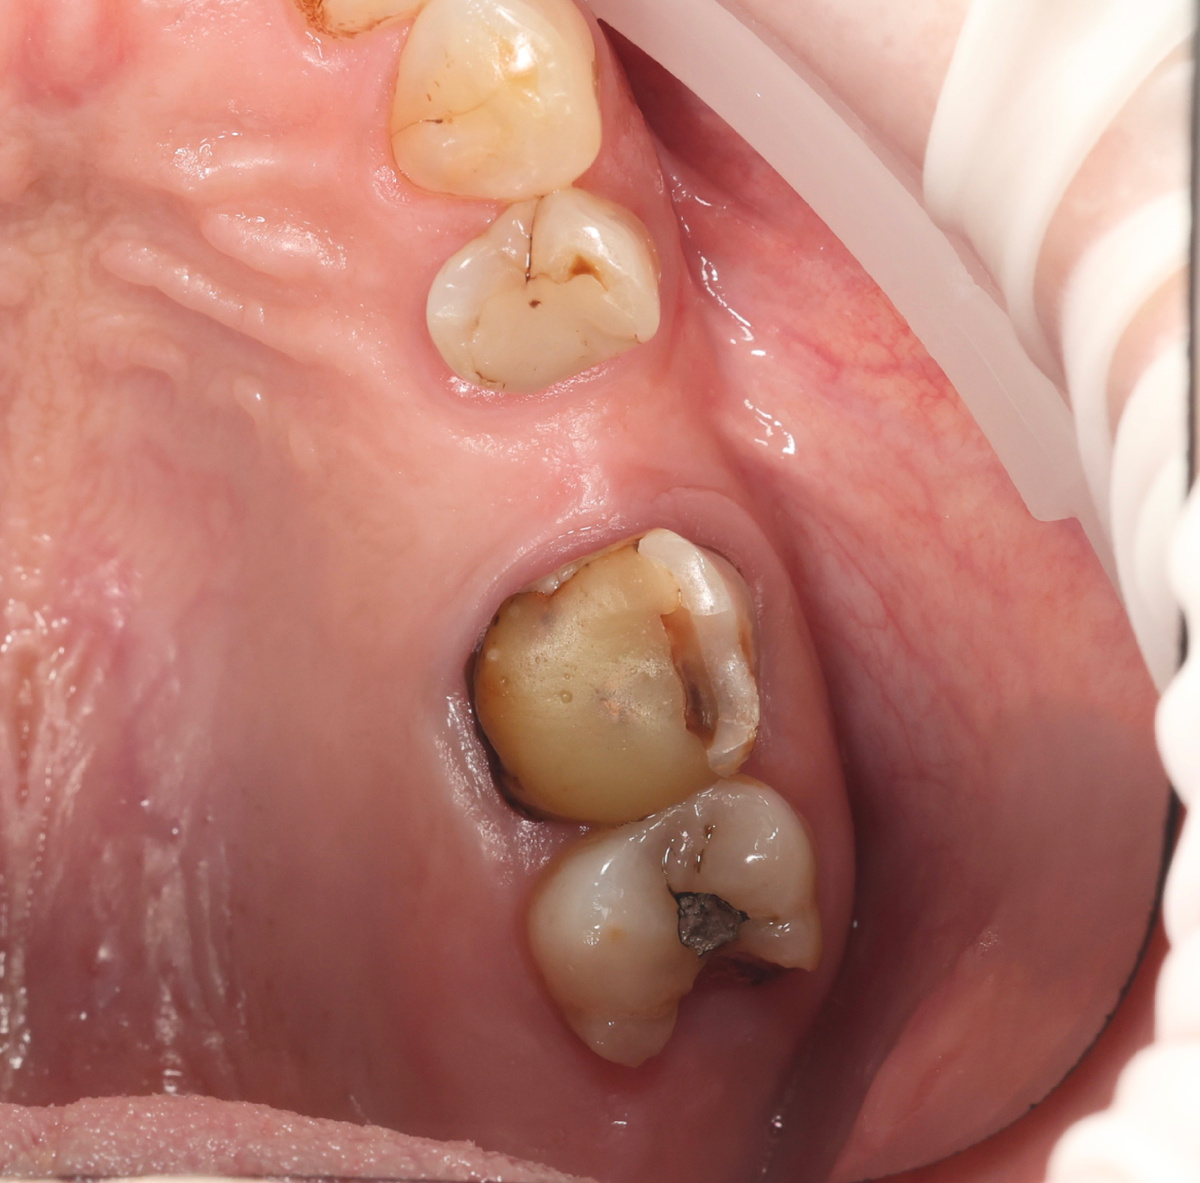

Середина июня. Зуб 1.7 - на вид, явный кандидат на удаление (на фото он крайний, половина коронковой части отсутствует). Огромный кариозный очаг, переходящий на корень, нерв мёртв 100%:

Зуб 1.7 до лечения

Но удалять не пришлось! Провели эндодонтическое лечение в два визита, вылечили каналы, запломбировали плотненько. Зуб сохранили.